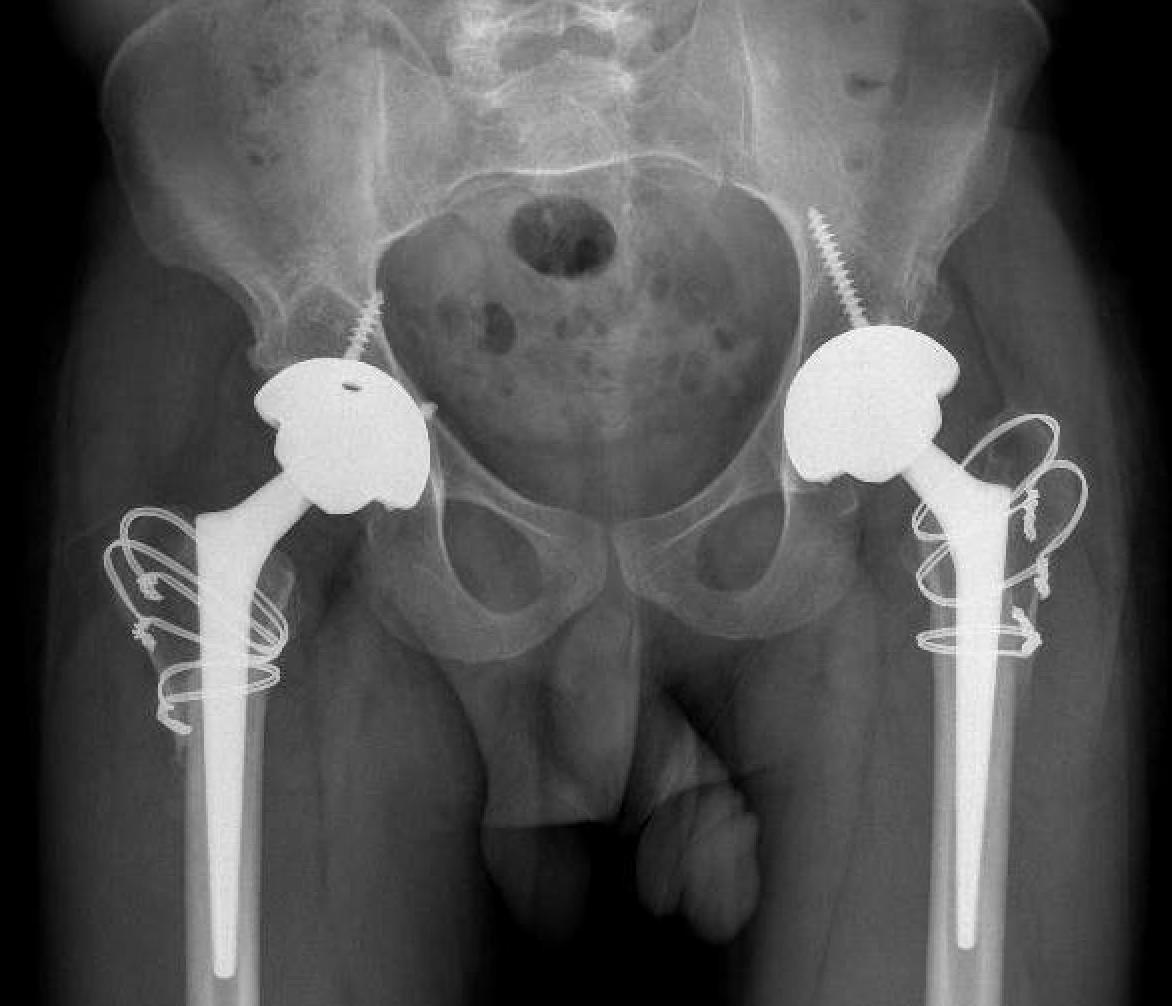

Technique

Option

- monoblock stem

- modular stem

Uncemented stem

Modular stem

Trochanteric slide

Results

Hanna et al Arch Orthop Trauma Surg 2017

- 6 studies and 245 THA in Perthes

- intra-operative fracture 11% reduced with used of modular stems

- sciatic nerve palsy 3% associated LLD 1.9 cm and previous surgery

- 99 THA for Perthes

- follow up 8 +/- 5 years

- 10% revision rate

- 9% intraoperative fracture (mostly femur)

- 3 sciatic nerve injury with lengthening of 2.2 +/- 1 cm